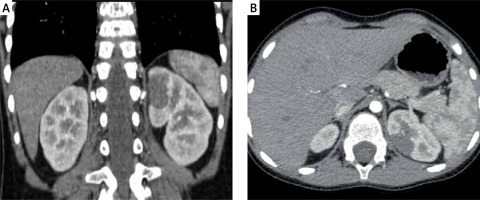

The mean tumor volume before and after chemotherapy was 174.4 ml (range: 14.7–501 ml) and 32.8 ml (range: 4.3–68 ml) respectively. Seven nephrectomies and one left heminephrectomy (NSS) (tumor volume 14.7 ml before chemotherapy (Photos 1 A, B) and 4.3 ml after chemotherapy (Photos 2 A, B)) were performed. LN was performed via the transperitoneal approach in all cases. No patients had an intraoperative tumor rupture. Median operative time for LN was 120 min (range: 100–195 min). The operative time for laparoscopic NSS was 210 min. No conversions to open surgery were needed. The specimen was extracted in a bag without morcellation in all cases. The umbilical trocar was removed. An endobag was inserted through the incision. The specimen was placed into it, and the abdominal cavity was deflated. For the extraction, the umbilical incision was extended 1–2 cm up and down according to the size of the specimen. All children had an attempt of lymph node sampling. Their number per pathology assessment ranged from 0 to 5 (median 2). In only one patient the number of harvested lymph nodes was zero. In this case no lymph nodes were observed visually and adipose tissue in the station which should contain small lymph nodes was removed. In the remaining patients the number of sampled lymph nodes was 2 in 5 cases, 3 in 1 case and 5 also in 1 case. All analyzed lymph nodes were negative for malignancy. The mean time of hospitalization was 3.5 days (range: 2–17).

Photo 1

A, B – Computed tomography scan of tumor at diagnosis showing an upper pole renal mass (tumor volume 14.7 ml)